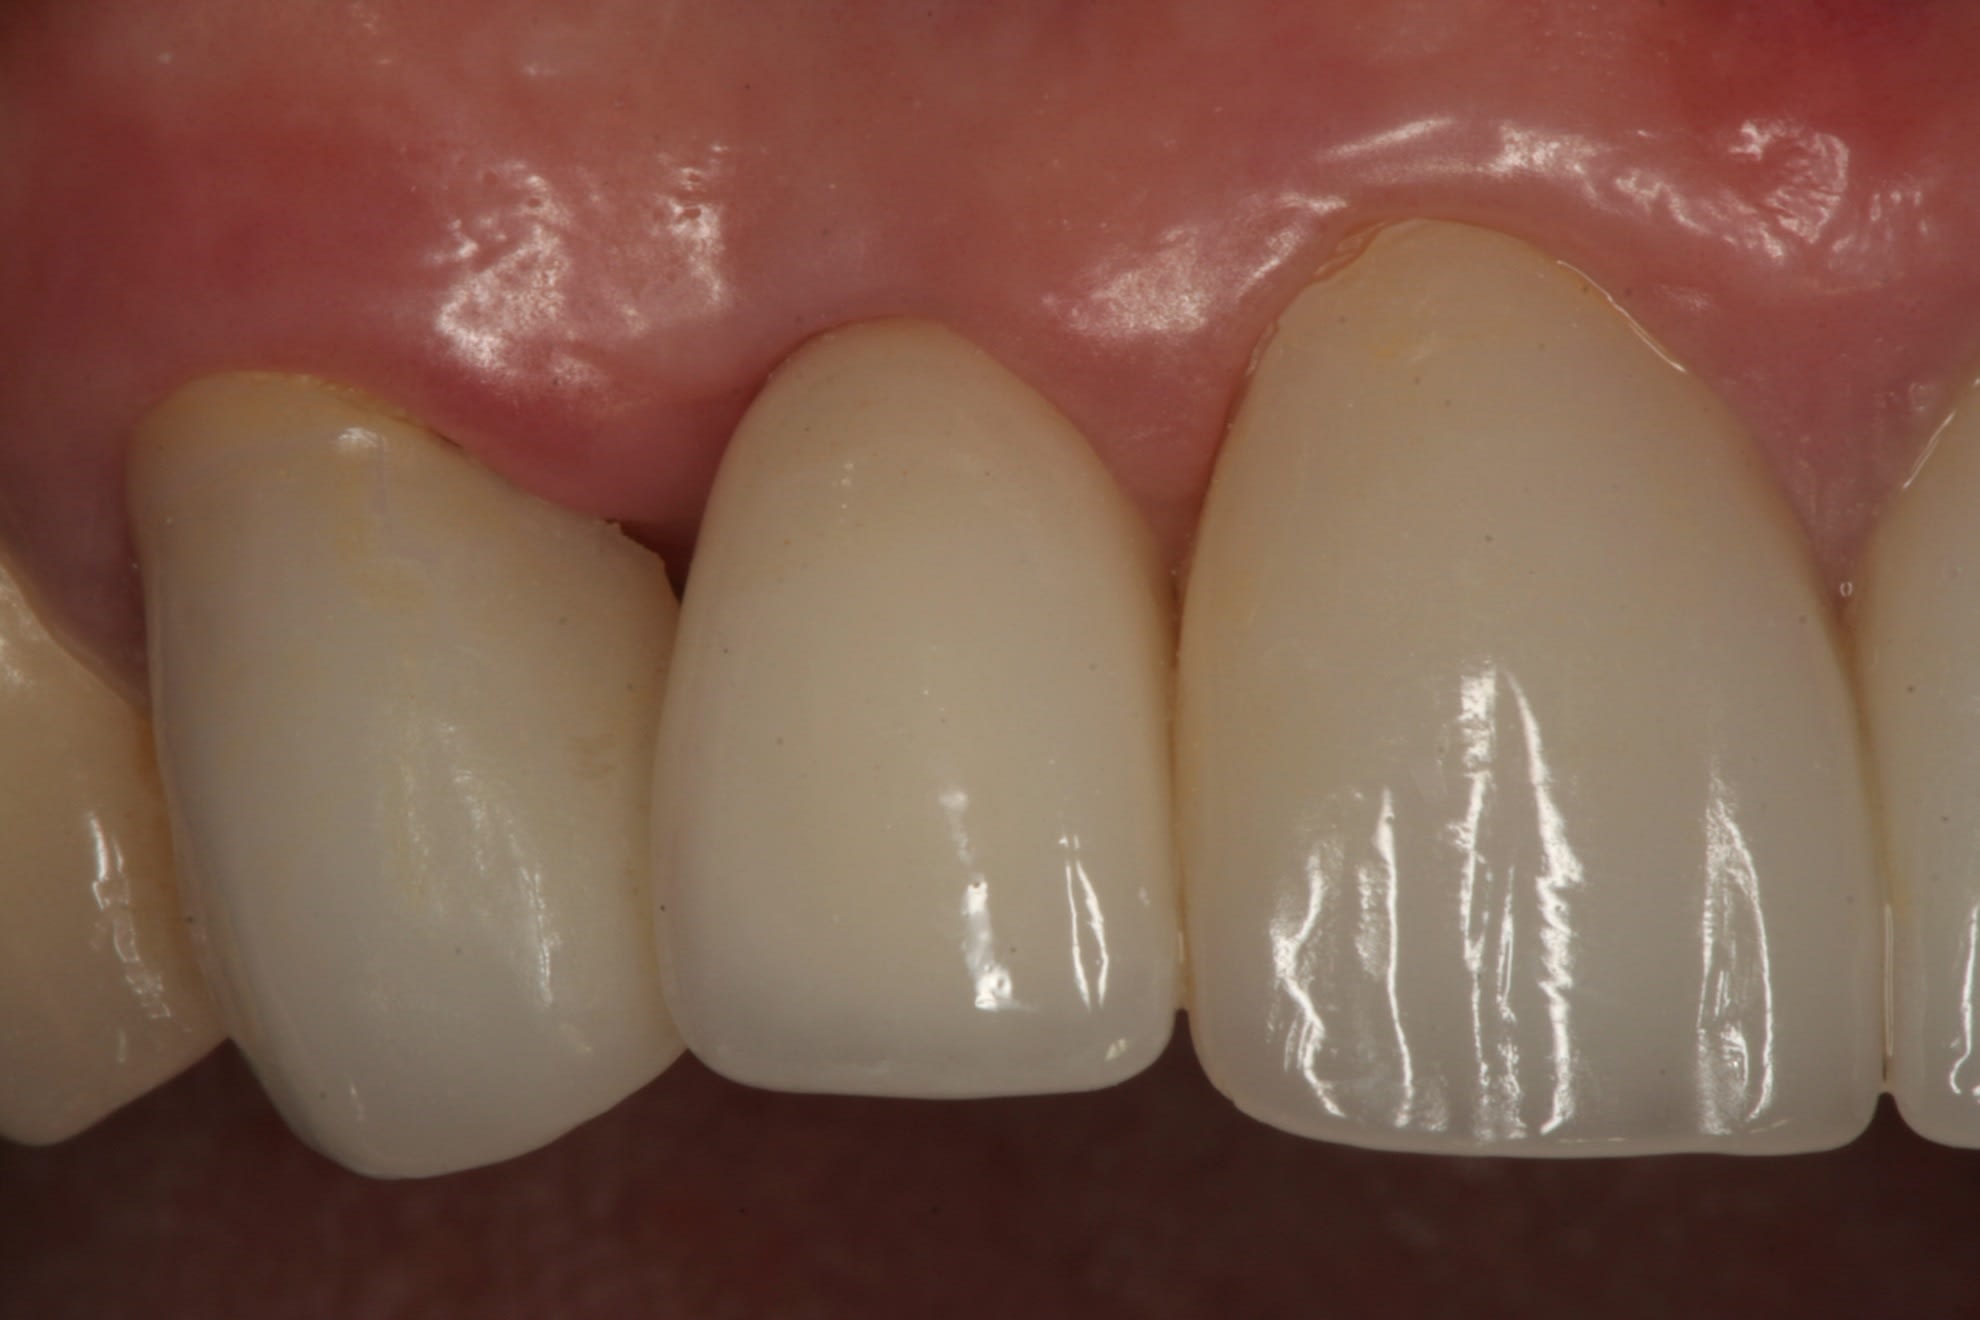

The final impression (closed tray) was obtained in April 2012. The final ceramic crowns (IPS e.max Ceram) and custom porcelain-veneered, regular-diameter (RD) UCLA abutments (Genesis; and Creation CC, Jensen Dental, www.jensendental.com) (Figure 24, shown with PFM crowns and retention screws) were delivered in May 2012. Using a platform-switched connection, the abutments were torqued to 30 Ncm, the access holes sealed with Teflon, and the final crowns cemented with RelyX Unicem. Figure 25 through Figure 28 show the final IPS e.max Ceram crowns from periapical, facial, and incisal views, with a midfacial PD of 3 mm at the 18-month follow-up (Visit 7). A thick biotype is evident in Figure 26, as determined by the inability to detect the outline of the periodontal probe inserted below the restoration’s gingival margin.50 This image also demonstrates an excellent esthetic outcome.

After this visit, additional restorative work was completed on teeth Nos. 6 and 7. Figure 29 and Figure 30 (retracted and smile views, respectively, at 3 years, Visit 8) show the excellent esthetic outcome registered during the 3-year postoperative period.